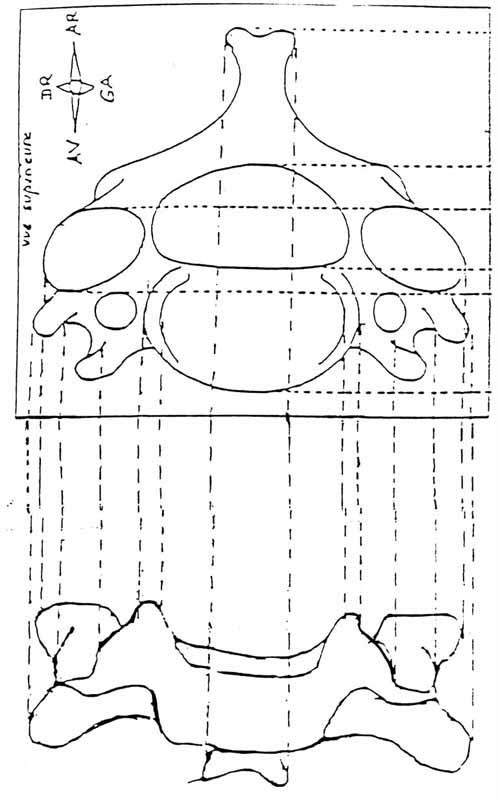

Commençons par le cervical, la suite viendra. Rachis cervical : radiographie, incidence antéro-postérieure

1. Axis

2. Processus transverse

3. Corps vertébral

4. Trou de conjugaison

5. Uncus

6. Disque intervétébralRachis cervical : radiographie, incidence de profil

Rachis cervical:  Rachis dorsal: Rachis dorsal:  Rachis lombaire: Rachis lombaire:   1. Processus articulaire supérieur 2. Pédicule droit 3. Processus transverse droit 4. Isthme 5. Processus articulaire inférieur 6. Lame opposée 7. Processus transverse opposé 8. Epineuse 9. Interligne articulaire postérieure 10. Processus articulaire inférieur opposé 11. Processus articulaire supérieur opposé Pour ce qui est de la radioanatomie; nous te laissons le soin d'apprendre tout cela grâce aux livres à ta disposition et à tes stages surtout!  Nous avions commencé une liste de livres de radiologie; à toi de t'en servir et bonnes recherches! Si tu souhaites trouver d'autres correspondances, si quelques détails t'interpellent n'hésite pas à poser des questions précises! Bon courage la marmotte!